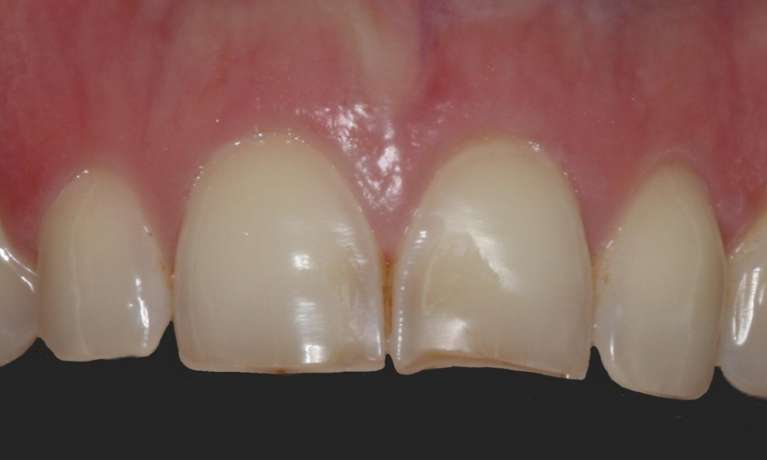

This case showcases the successful outcome of a gum graft procedure performed around an existing dental implant. Initially, the patient experienced gum recession around their implant, which can sometimes expose the implant's margin or simply lead to an uneven gum line.